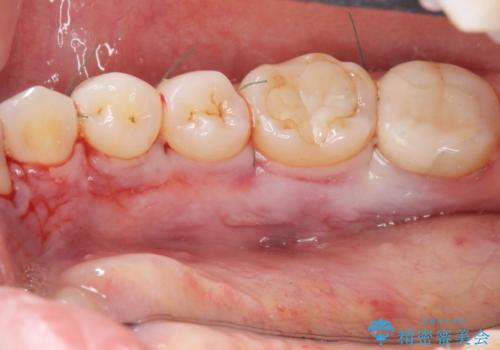

- 徐々に大きくなってきた骨隆起の除去を希望され来院されました。

下顎隆起を切除することで舌を収めるスペースを確保し発音のしやすさの向上を図ります。

手術は約1時間弱で終了し、術後もほとんど腫れは出ません。